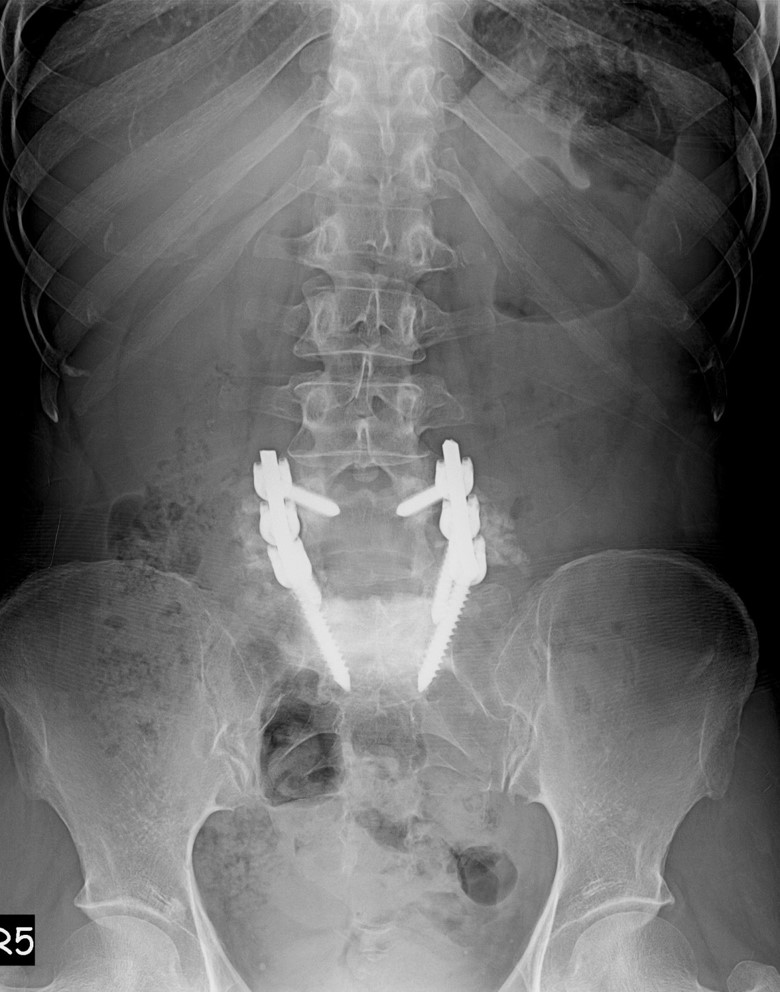

51 Yaşında Kadın Hasta

Bel ve sağ bacak ağrısı

NM normal

Ameliyat Öncesi

Ameliyat Sonrası